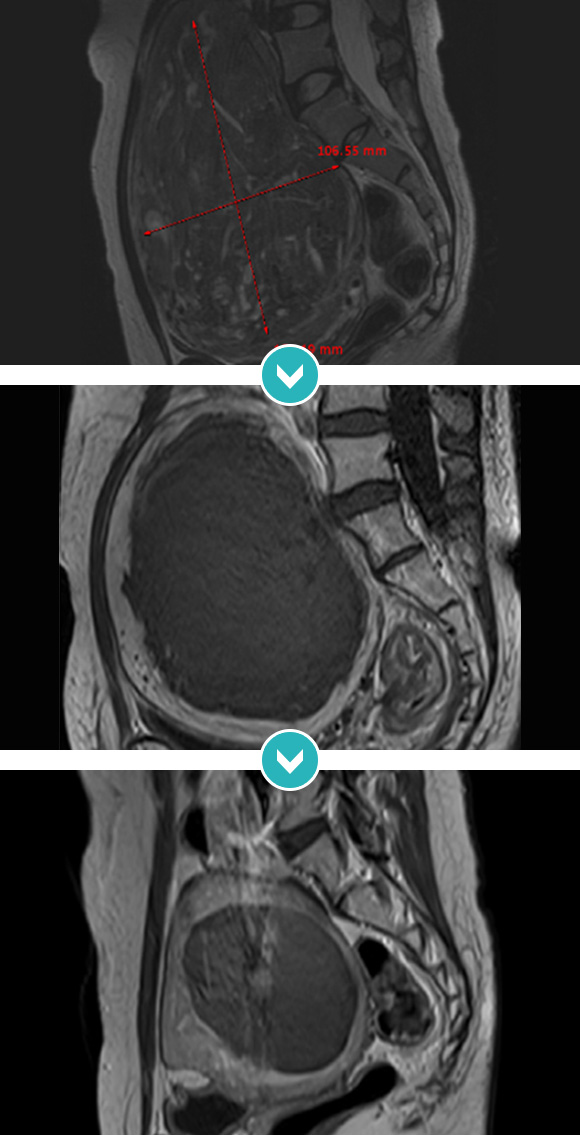

점막하 자궁근종 및 2.5cm 근층내 자궁근종 등 다발성 자궁근종 하이푸 치료 후 90%이상 괴사, 6개월 추적관찰